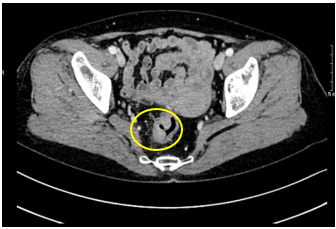

- CT scanner ổ bụng :

Hình 2: Hình ảnh khối u trực tràng giữa qua chụp CLVT. Trực tràng giữa thành dày không đều quanh chu vi, chỗ dày nhất 17mm, trên đoạn dài 40mm, không rõ cấu trúc lớp, ngấm thuốc mạnh sau tiêm.